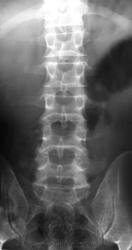

Переходный пояснично-крестцовый позвонок за счет тенденции к правосторонней сакрализации, развившийся на этом фоне сколиоз (с торсией, вызвавшей предыдущий пост), с развившемя на этом фоне остеохондрозом преимущественно сегмента L5-S1.

Есть вопросы по структуре крестца ( неоднородное затенение в проеции дуг на уровне СоII-CoIV- изменение структуры костной ткани ?)... но может быть наслоения кишечника.

да тут же грыжи Шморля огроменные во всех позвонках по нижним замыкательным,снижение высоты L4,5-скошенность передних углов,остеофиты,ретролистез L5,снижение высоты дисковL4-S1,наверное "распорка"-косвенный симптом грыжи диска,нет тут переходных позвонков -поясничных 5,нерезкая асимметрия поперечных L5-незначимая(ИМХО). Он же ГАСТАРБАЙТЕР-молодой мужик,наверное тяжести таскал,надорвал спину-причем явно не вчера,а м.б у него исход Шойермана-Мао (плюс ко всему )судя по форме позвонков.Уф -извините,не выдержал просто-вот такой вот остеохондроз-вроде бы незначительный- и болит больше всего,пока отёк костного мозга в теле позвнка не "переродится" в жир и склероз и не заблокируется сегмент спондилофитами. А болеть может усе,что угодно,от миофасцита(продуло,надрыв-растяжение мышц-связок-сухожилий),до того-же остеохондроза в момент обострения -то-бишь воспаления. А грыжа боль дает ,когда продавливает связку-неважно какую связку-ведь в связках большое количество болевых рецепторов,а если уж очень большая -при компресси "конского хвоста"должна быть соответствующая симтоматика.Деструкции -не вижу,асимметрия в корнях дужек L4-наверное за счёт торсии.Еще раз извините ,я в первый раз пишу,хотя за сайтом слежу больше 2х лет.

4. А все мои смущения по поводу данного снимка (рис.1) укладываются не в разрежение структуры дужек L3-4-5 по сравнению с L2 (рис.2); не в псевдопросветление задненижнего сектора тела L5, верхний контур которого образован на самом деле нижним краем основания дужки и выходит за пределы тела (рис. 3); на в кажущееся нарушение структуры крестца, хотя все контуры сегментов, сакрального канала и даже остаточных линий дисков четко отслеживаются (рис. 4), а в наличие грыжевой пролабации типа Поммера каудальной пластины L5, близко расположенной к заднему краю (рис. 5), что при наличии признаков вентральной грыжи диска L5/S1 в сочетании с ретролистезом 1 степени не исключает и заднюю грыжу этого диска.

Помещая этот случай, я имел в виду узнать мнения коллег по поводу пролабирования (разной степени выраженности) замыкающих пластинок всех пяти поясничных позвонков. Согласитесь коллеги, подобная рентгеновская картина не является нормой для мужчины в расцвете лет. Такое мы часто видим у пожилых и особенно старых женщин, привычно связывая такой феномен с инволютивной спондилопатией. Между тем, для меня это не первый гастарбайтер с такой рентгеновской картиной позвонков Мне думается, здесь патология, по-видимому, не дисков, а позвонков. Не нахожу я здесь сколько-нибудь существенного снижения м/п дисков, да и других признаков остеохондроза не нахожу. Как патогенетический механизм я рассматриваю ослабление спонгиозного костного матрикса или также минеральной фазы кости. Наверное, если не остеопороз, то остеопения здесь имеется. А этиология, на мой взгляд, коренится в неполноценном питании данного контингента: дефицит животного белка, витаминов (особенно витамина D), кальция. Это связано с экономическими факторами в первую очередь. И при этом значительные физические нагрузки. Ещё подобную картину приходится встречать у молодых женщин, задолго до менопаузы. В этом случае, думаю, сказывается пагубная роль разных нелепых, порой совершенно дурных диет, цель которых достичь значительного похудания любой ценой и при этом практикуются серьёзные физ. нагрузки на позвоночник (вроде шейпинга).